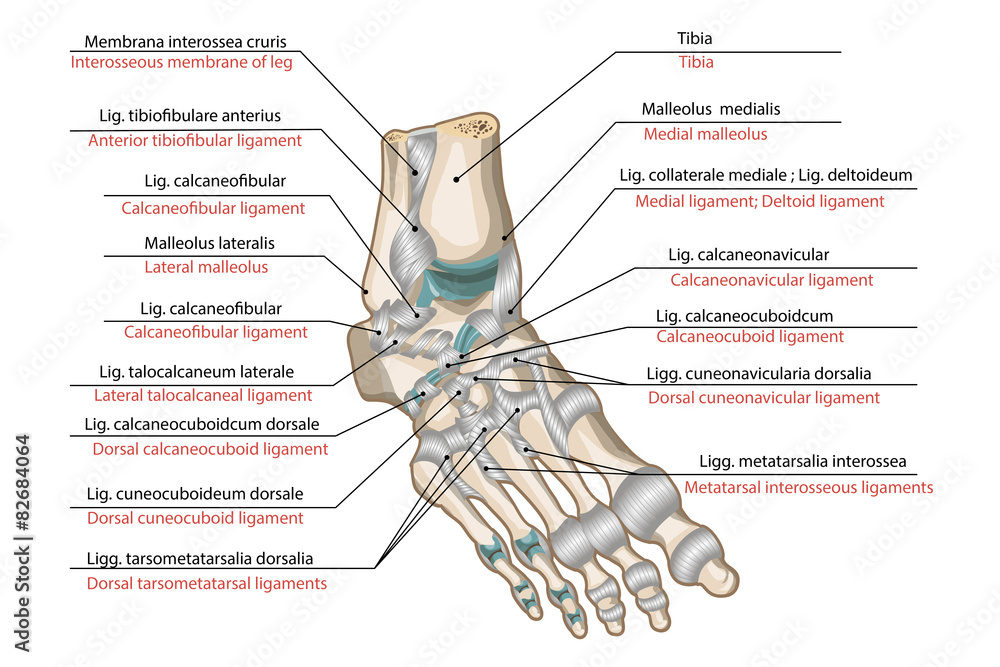

focusedcollection.comLigaments And Joints Of The Foot Stock Vector | Adobe Stock

focusedcollection.comLigaments And Joints Of The Foot Stock Vector | Adobe Stock